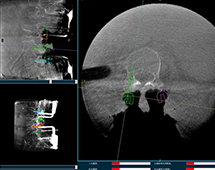

機器人輔助腰椎后路側彎矯形手術方案解析

機器人輔助腰椎后路側彎矯形手術是什么原理?下面帶來一例機器人輔助腰椎后路側彎矯形手術方案,該手術在南京醫科大學第二附屬醫院進行,所用設備為普愛脊柱外科手術機器人PL300B+三維C形臂PLX7500A。...

使用機器人做椎體成形術的過程是什么樣的

國內醫院使用骨科機器人來做椎體成形術的案例并不少見,該手術的實施過程是什么樣的呢?以普愛醫療的骨科手術機器人PL300B為例,其輔助進行的一例胸腰椎壓縮性骨折經皮椎體成形術的過程如下:...